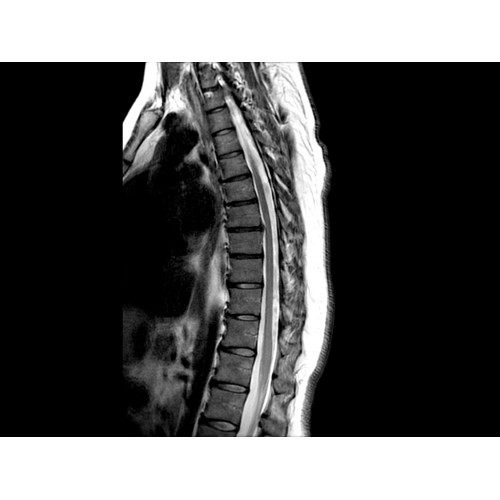

• Визуализация всего позвоночника слиянием двух участков — получить изображение всего позвоночника можно намного быстрее.

• Градиентная подсистема eXtreme — мощная градиентная подсистема для исследования тела характеризуется градиентом 34 мТл/м и скоростью нарастания градиента 150 Тл/м/с по каждой оси, что обусловливает быстроту, точность и высокую воспроизводимость сканирования.

• Цифровой РЧ-приемник OpTix — эксклюзивная оптическая РЧ-система увеличивает четкость сигнала и его интенсивность, формируя чистые и резкие изображения.